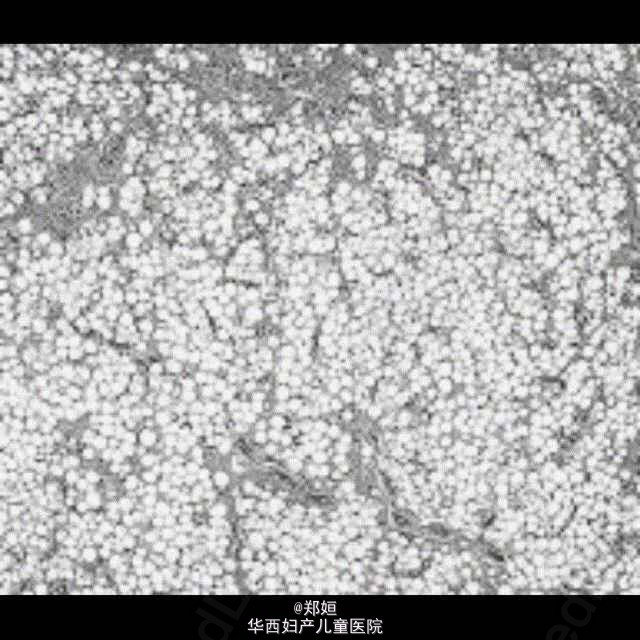

50岁女性,外阴无疼痛性膨胀数月

查体后初步诊断为外阴血管粘液瘤

初步诊断为外阴血管粘液瘤 行肿瘤的局部切除

恢复良好,无复发 外阴血管肌纤维母细胞瘤是发生于外阴、会阴及腹股沟区的具有一定临床病理特征的浅表软组织肿瘤。较为少见。血管肌纤维母细胞瘤发病比较隐匿,常常是患者无意中发现外阴肿物,病程数月至数年,一般无疼痛。肿物大多位于大阴唇和外阴区,肿瘤边界清楚。本病很少能在术前做出明确诊断,肿物局部切除可治愈,一般不复发。